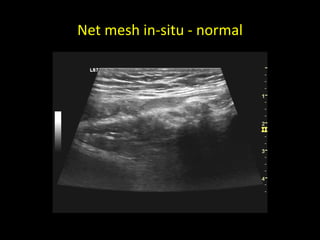

Net-mesh

Net mesh in-situ - normal

Netmesh